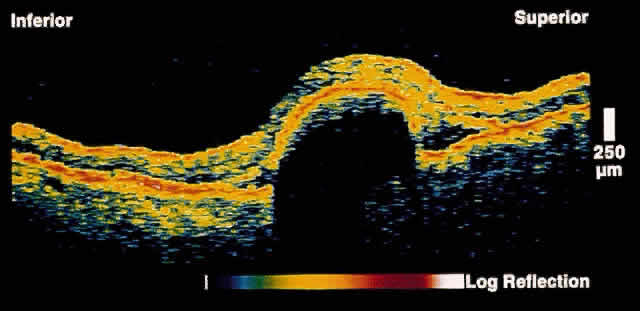

Central serous chorioretinopathy (CSCR) is characterized by detachment(s) of the neurosensory retina caused by one or more focal leaks at the level of the RPE. When small or shallow, these serous detachments may be difficult to detect clinically. OCT images of such areas demonstrate elevation of neurosensory retina by the presence of subretinal fluid.12 The well-defined contrast in optical reflectivity between the nonreflective serous fluid and the more highly reflective posterior boundary of the neurosensory retina allows OCT images to be highly sensitive to even small neurosensory detachments. Indeed, OCT images may show the presence of neurosensory detachments not detectable by clinical examination. The ability of OCT to image the same retinal area on subsequent visits allows for the longitudinal monitoring of the clinical course of the serous detachment in this disease (Figs. 2 and 3). OCT is particularly useful when thisdisease presents in older patients. The presence of drusen and pigmentary changes in these patients may lead to the erroneous conclusion that a choroidal neovascular complex is the cause of the neurosensory detachment. OCT may be able to provide additional diagnostic information in these patients by excluding the existence of a choroidal neovascular membrane or abnormalities in the choriocapillaris/RPE layer.

Fig. 2. OCT image shows a neurosensory detachment secondary to central serous chorioretinopathy. The difference in optical reflectivity between the posterior boundary of the neurosensory retina and the underlying serous fluid allows even small areas of elevation to be detected.

Fig. 3. Several weeks later, an OCT taken through the same area reveals partial resolution of the neurosensory detachment.